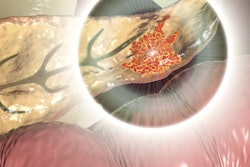

Prof. Okan Akhan from Ankara. Courtesy of BIR.The 33-minute discussion focuses on percutaneous biopsy and why certain patients may benefit from this treatment, common potential postoperative complications and how these can be managed, and palliative care using IR. It also covers treatment options for patients with locally advanced pancreatic adenocarcinoma as well as patients with metastatic disease.

"Interventional radiology provides a wide range of safe and effective treatment modalities for pancreatic cancer patients in every step of the disease, starting from initial diagnosis to the end," Akhan said. "Despite the poor prognosis and high mortality of the disease, IR provides highly effective, minimally invasive solutions for pancreatic cancer patients to improve their quality of life."